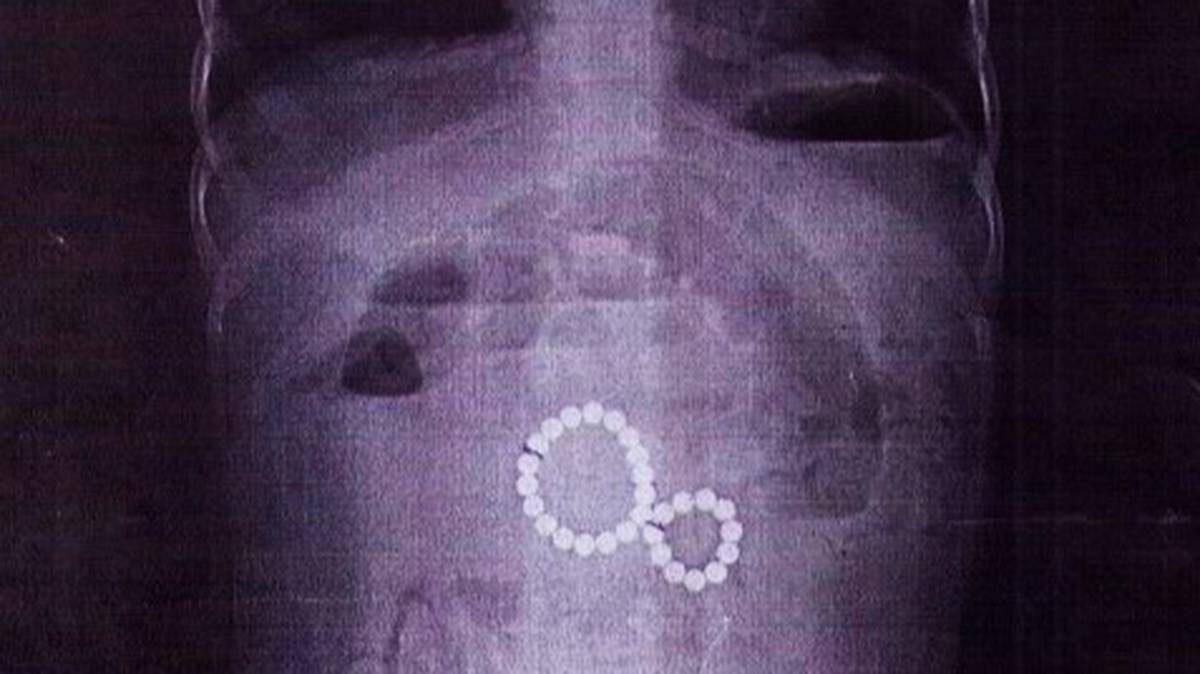

Двухлетняя девочка проглотила 29 магнитных шариков в Иркутске

Фото: ВКонтакте / Детская областная больница Иркутск

В Иркутске двухлетняя девочка была экстренно прооперирована после того, как проглотила 29 магнитных шариков. Об этом сообщили в пресс-службе городской детской больницы.

Ребенок поступил в тяжелом состоянии с симптомами кишечной непроходимости и кровавой рвотой. Рентген показал, что магниты, попав в разные отделы кишечника, образовали опасное сцепление, вызвав внутреннюю грыжу и угрозу разрыва стенки кишки.